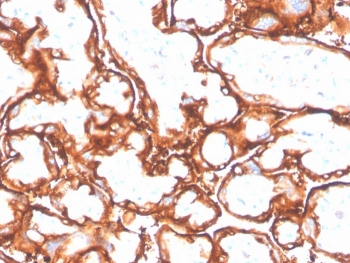

EGFR L858R Antibody Placenta IHC. Immunohistochemistry analysis of FFPE human placenta tissue stained with EGFR L858R mutation-specific antibody detecting mutant EGFR, clone GFR/4564R. Trophoblastic epithelial cells show membranous staining outlining cell borders. As normal placenta is not expected to harbor the L858R mutation, this signal should be interpreted cautiously and may reflect non-specific or low-level cross-reactivity. Hematoxylin counterstain highlights nuclei in blue. HIER: boil tissue sections in pH 9 10 mM Tris with 1 mM EDTA for 20 min and allow to cool before testing.

EGFR L858R Antibody Placental Trophoblast IHC. Immunohistochemistry analysis of FFPE human placenta tissue stained with EGFR L858R mutation-specific antibody detecting mutant EGFR, clone GFR/4564R. Trophoblastic epithelial cells show membranous staining outlining cell borders with focal cytoplasmic signal. As normal placenta is not expected to harbor the L858R mutation, this staining should be interpreted cautiously and may reflect non-specific or low-level cross-reactivity. Hematoxylin counterstain highlights nuclei in blue. HIER: boil tissue sections in pH 9 10 mM Tris with 1 mM EDTA for 20 min and allow to cool before testing.